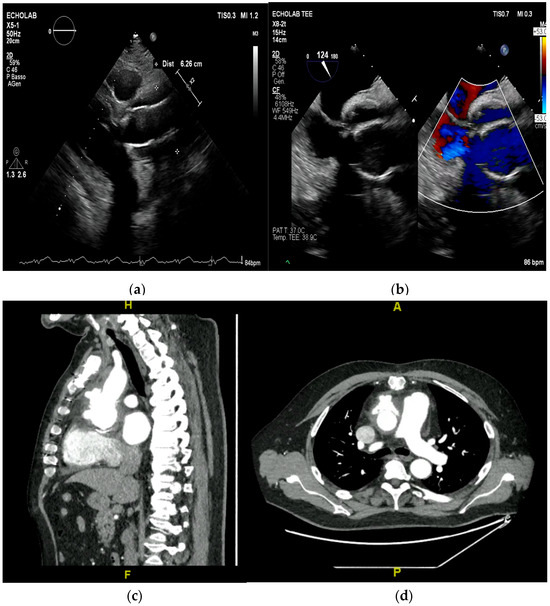

Multimodality Imaging in Infective Endocarditis: A Clinical Approach to Diagnosis

by Leonardo Brugiatelli, Francesca Patani, Carla Lofiego, Martina Benedetti, Irene Capodaglio, Pongetti Giulia, Francioni Matteo, Paolini Enrico, Nazziconi Marco, Kevin Maurizi, Furlani Giulia, Massari Arianna, Luciani Simone, Anselmi Benedetta, Gatti Chiara, Schicchi Nicolò, Fogante Marco, Tarsi Giovanni, Dello Russo Antonio, Di Eusanio Marco, Marini Marco and Fabio Vagnarelliadd Show full author list remove Hide full author list

Medicina 2025, 61(12), 2241; https://doi.org/10.3390/medicina61122241 - 18 Dec 2025

Infective endocarditis (IE) is a life-threatening condition with a rising incidence, demanding rapid and precise diagnosis. While echocardiography remains the cornerstone of initial evaluation, its limitations in complex cases—such as those involving prosthetic valves or cardiac devices—are well-known. This review synthesizes current evidence [...] Read more.

Infective endocarditis (IE) is a life-threatening condition with a rising incidence, demanding rapid and precise diagnosis. While echocardiography remains the cornerstone of initial evaluation, its limitations in complex cases—such as those involving prosthetic valves or cardiac devices—are well-known. This review synthesizes current evidence and guidelines to outline a practical, multimodality imaging approach for IE. We emphasize that integrating advanced techniques like cardiac computed tomography (CT) and [18F]-fluorodeoxyglucose positron emission tomography/computed tomography (FDG PET/CT) early in the diagnostic pathway, particularly in high-risk scenarios, significantly enhances diagnostic certainty, guides therapeutic decisions, and improves patient outcomes. A tailored imaging strategy, driven by clinical presentation and integrated within a multidisciplinary endocarditis team, is paramount for modern IE management. Full article

(This article belongs to the Special Issue Diagnosis and Treatment of Valvular Heart Diseases)

Show Figures

Figure 1